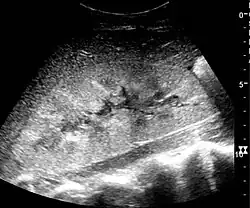

In medical imaging, the acute changes in the kidney are often examined with renal ultrasonography as the first-line modality, where CT scan and magnetic resonance imaging (MRI) are used for the follow-up examinations and when US fails to demonstrate abnormalities. In evaluation of the acute changes in the kidney, the echogenicity of the renal structures, the delineation of the kidney, the renal vascularity, kidney size and focal abnormalities are observed.[20] CT is preferred in renal traumas, but US is used for follow-up, especially in the patients suspected for the formation of urinomas. A CT scan of the abdomen will also demonstrate bladder distension or hydronephrosis.[21]

Renal ultrasonograph of acute pyelonephritis with increased cortical echogenicity and blurred delineation of the upper pole[20] -

Renal ultrasonograph in renal failure after surgery with increased cortical echogenicity and kidney size. Biopsy showed acute tubular necrosis.[20] -

Renal ultrasonograph in renal trauma with laceration of the lower pole and subcapsular fluid collection below the kidney[20]